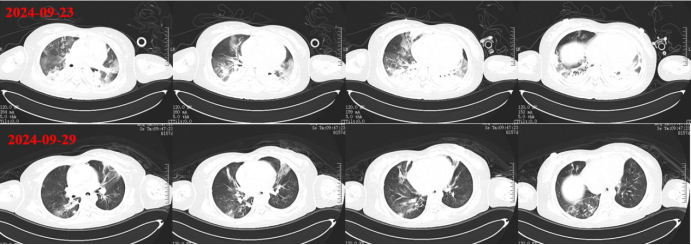

9月23日在ECMO支持下带患者外出行胸部CT检查:上肺渗出影斑片影双下肺实变,左下肺实变更明显(图7)

图片

7  患者胸部CT(2024-09-23)

928日外出复查胸部CT:双肺渗出和实变明显吸收改善(图10,图11)

10  复查胸部CT(2024-09-29)

11  患者胸部CT对比